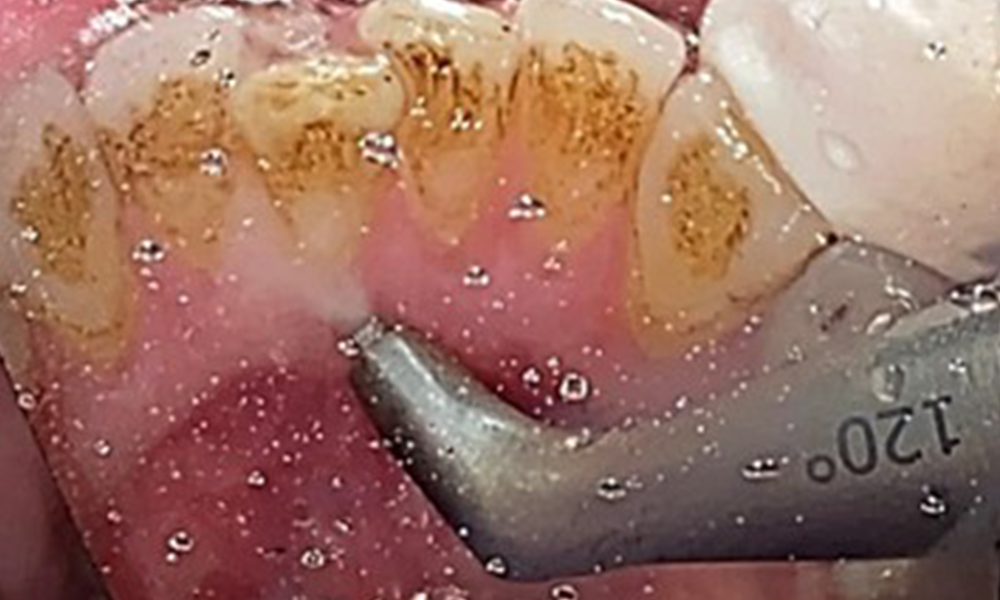

The objective would be to control disease risk by removing supragingival and subgingival biofilm. The instruments can be selected based on patient needs. First, calculus and any concretions must be removed using ultrasonic and/or manual instruments (Fig. 10).

Use of a piezo-driven ultrasonic device in the lingual area near 36 (Proxeo Ultra, W&H, shown here)

Fig. 10 Use of a piezo-driven ultrasonic device in the lingual area near 36 (Proxeo Ultra, W&H, shown here), © Dr R. Krapf

Discolouration caused by nicotine and tea consumption can be removed easily using an air polisher (Fig. 11).

Air polishing system use in the mandibular frontal lingual area (here, Proxeo Aura, W&H)

Fig. 11 Air polishing system use in the mandibular frontal lingual area (here, Proxeo Aura, W&H), © Dr R. Krapf

When using more abrasive powder, it is essential to work from a cervical to coronal direction and never point the outlet nozzle towards the gingiva to prevent potential emphysema. Good suction on the contralateral side is essential to reduce aerosol formation (Fig. 12).

Use of the air polishing system away from the sulcus with contralateral suction.

Fig. 12 Use of the air polishing system away from the sulcus with contralateral suction, © Dr R. Krapf